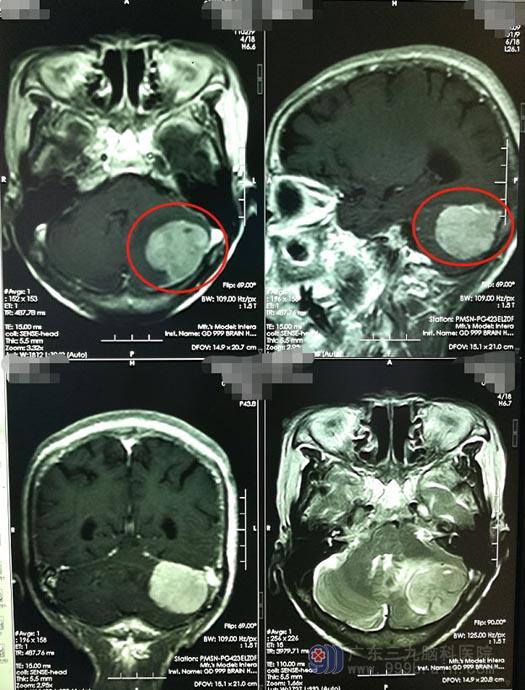

那天是午饭后,苏奶奶起身准备午休,突然一阵眩晕,随后出现呕吐。家人立即将奶奶送到当地医院,颅脑MR检查显示“左侧小脑幕脑膜瘤”,经过对症处理,苏奶奶眩晕呕吐症状有好转。医生说这个部位的肿瘤手术风险很大,术后可能会出现严重的后遗症。

为了让奶奶能得到更专业的治疗,家人带着她来到了广东三九脑科医院。入住神经外五科,进一步脑部检查发现:左侧后颅窝团块状占位性病变,大小为3.8cm×3.3cm×3.8cm,左侧小脑半球脑实质受压,导致轻度的脑积水;如果肿瘤进一步长大,就会对脑脊液循环通路造成影响,从而造成恶性颅高压的症状,患者可能会在短时间之内出现意识障碍、昏迷、甚至脑疝。尽早手术是治疗的首选。